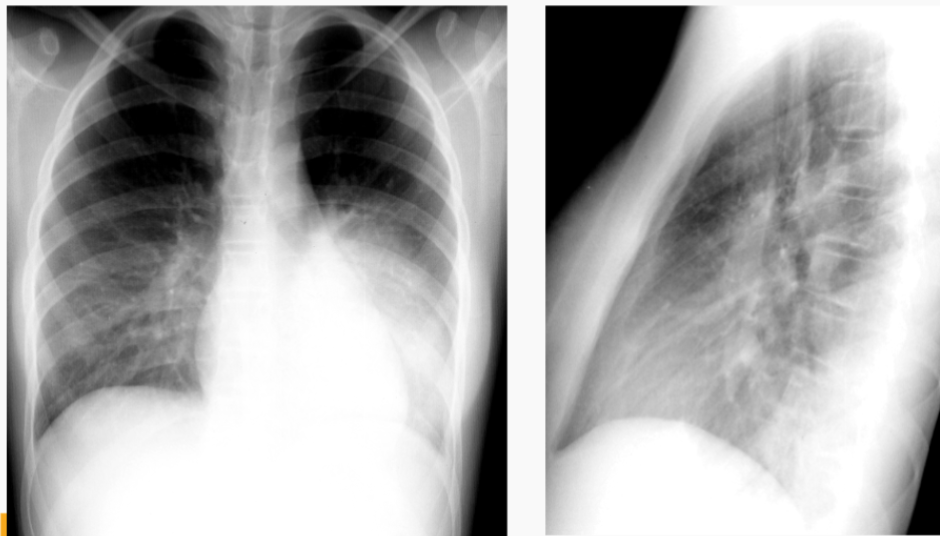

Which image represents the “spine sign” and what does this mean?

Right side is spine sign; means that there is something in the lungs (should go bright—>dark, not dark—>bright)